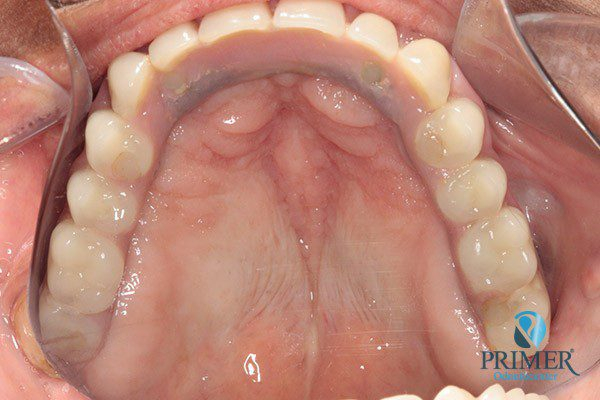

Realizado em: Agosto de 2012Detalhes do tratamento: Implantes instalados imediatamente após extrações de dentes inferiores e prótese fixa sobre implantes (instalada 72 horas após a cirurgia).

Fiz tratamento odontológico com Dr. Alexandre e Dra. Mariza. Foi muito bom, gostei muito e estou muito satisfeita. Com Dr. Alexandre fiz cirurgia e implante. Foi muito bom não sentir dor, foi perfeito. Com Dra. Mariza fiz prótese fixa sobre implante inferior e prótese total “normal” superior. Estou muito satisfeita com o trabalho deles!